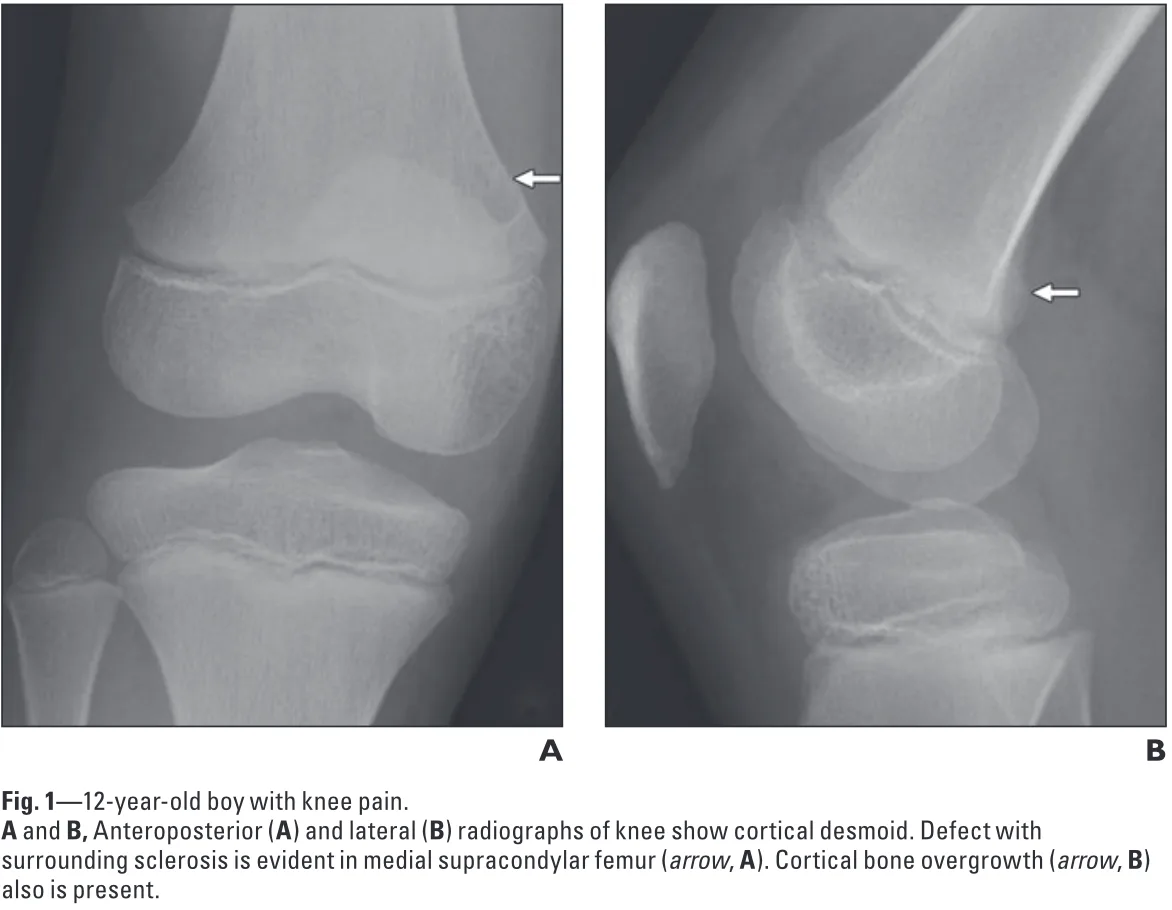

膝の痛みを主訴にX線を撮影したところ, 大腿骨遠位内後方に骨が盛り上がるような病変があり,

骨腫瘍が疑われたとのこと.

正面像(A)では, 大腿骨の内側部が透けるように写る病変が, 側面像(B)では, 骨が隆起するように写る病変がそれぞれ認められます.

X線写真を確認すると, 遠位大腿骨皮質骨不整 distal femoral cortical irregularity(以前は, 皮質デスモイドcortical dermoid, avulsive cortical irregularityなどと呼ばれていた)所見が疑われました.

遠位大腿骨皮質骨不整は, 小児期から青年期にかけて見られる, 骨腫瘍と誤認されやすい良性・一過性の病変です.

両側性のこともあり, 多くは無症状.

時間の経過とともに自然消失するため, 治療は不要です.